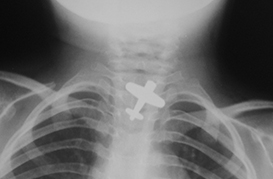

Cuerpo Extraño en Esofago